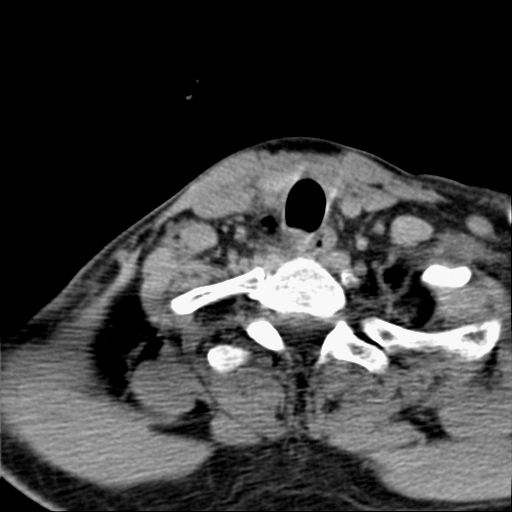

标题: CT23947 右颈部触及00.5x1.5cm质硬长形肿块,疼痛 [打印本页]

标题: CT23947 右颈部触及00.5x1.5cm质硬长形肿块,疼痛

右侧甲状腺病灶,建议增强或结合b超检查。

右甲状腺占位,建议增强。

甲状腺右叶占位病变,建议增强扫描。

甲状腺右侧叶占位,定性困难,建议增强。

右侧甲状腺低密度病灶,性质待定;建议行进一步检查。